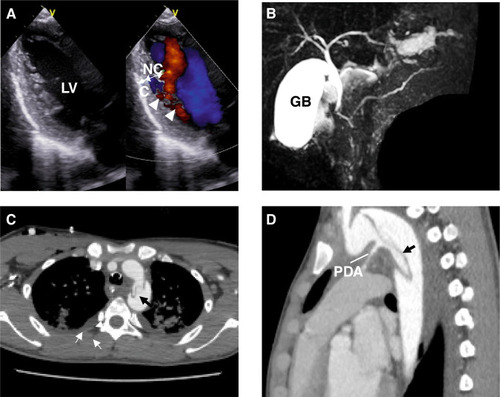

Echocardiography and magnetic resonance cholangio-pancreatography (MCRP) of the patient with the ACTA2 G148R variant. A An echocardiogram showing the left ventricular long-axis view during diastole. The ventricular wall of the left ventricle exhibits an outer compacted layer (C) and an inner non-compacted trabecular layer (NC), with deep recesses formed by the trabeculations (NC/C ratio 2.0). Color Doppler imaging shows blood infiltrating into the spaces between the trabeculae (arrowheads). B On MRCP, the main pancreatic duct exhibits a reverse Z-shape (arrows) in the head of the pancreas region. C, D Chest magnetic resonance imaging shows the descending aortic deviation. LV left ventricle, C compacted layer, NC non-compacted layer, GB gallbladder, PDA patency of the ductus arteriosus